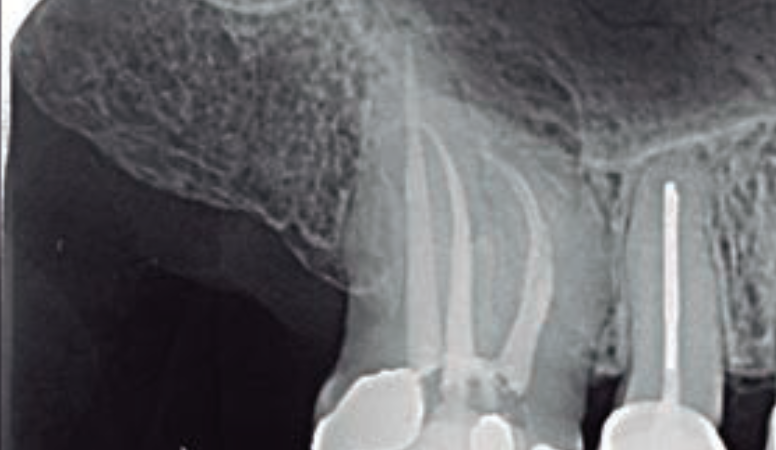

A tomografia computadorizada de feixe cônico faz aniversário! Entenda a mudança de paradigma na Odontologia.

Saiba porque a Prótese Dentária e a Endodontia são especialidades que devem ter grande desempenho nos próximos anos em função da tecnologia de imagem digital